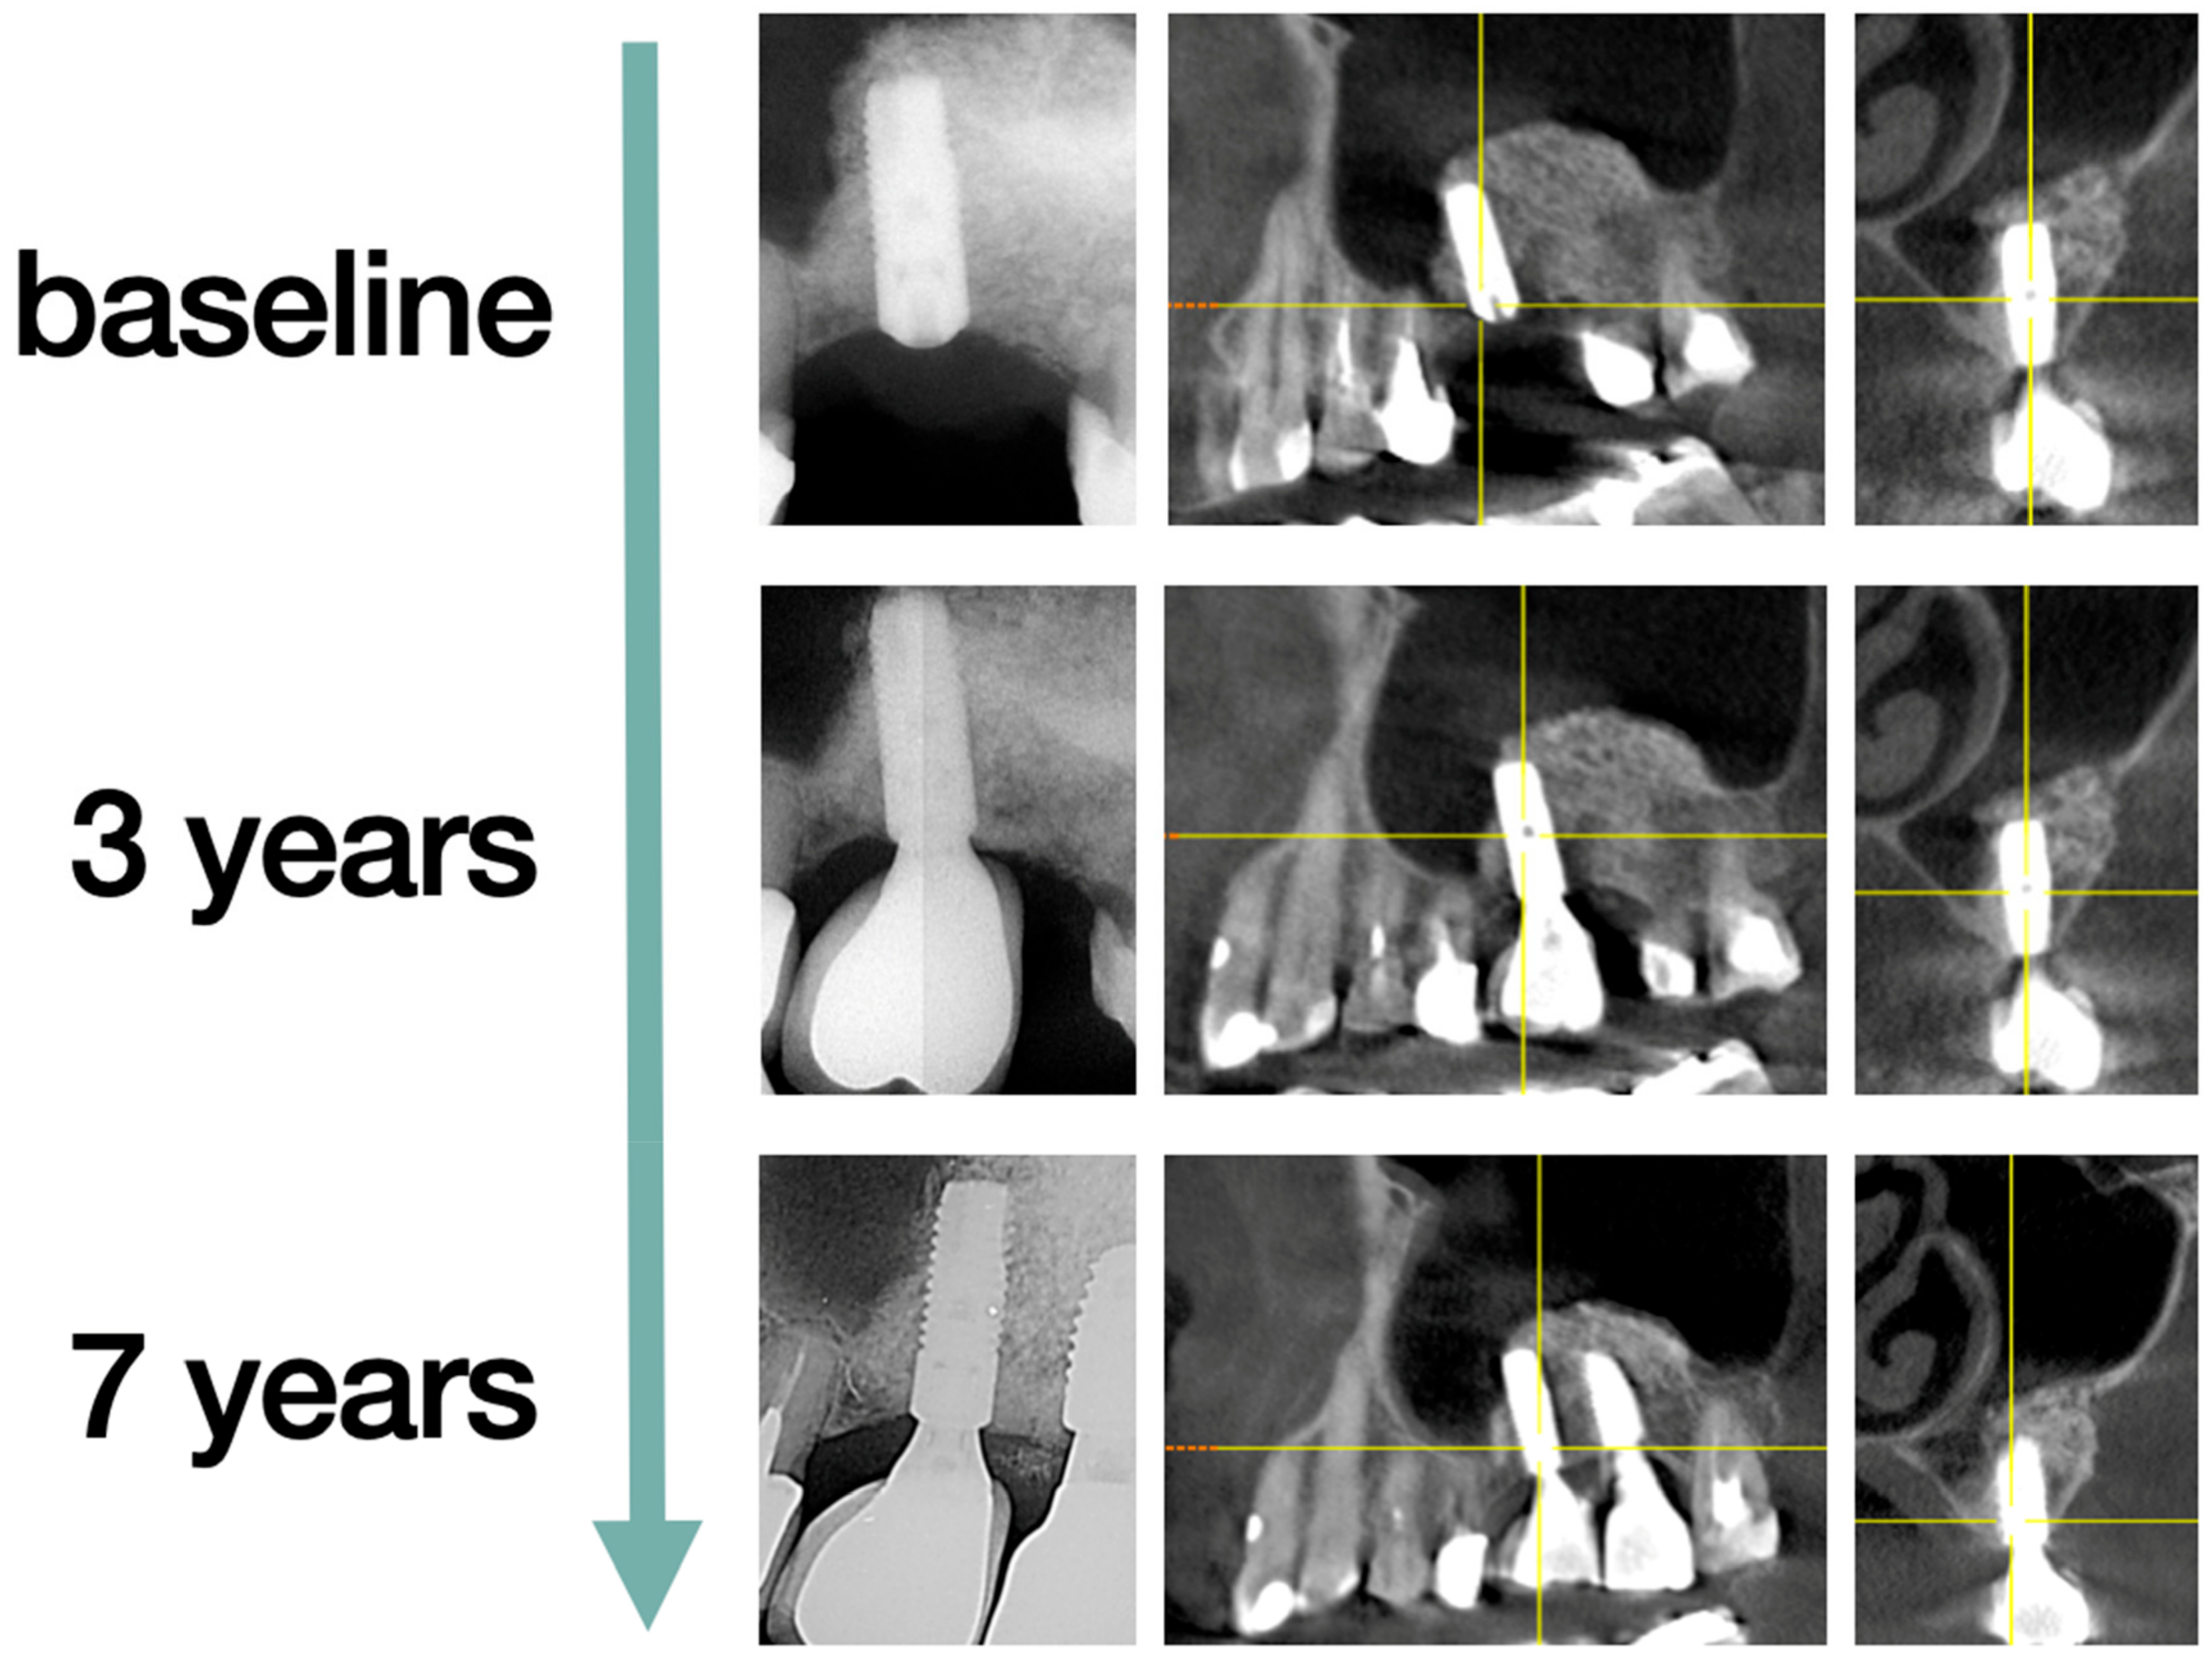

3.4. Marginal Bone Loss

3.5. Technical Complications